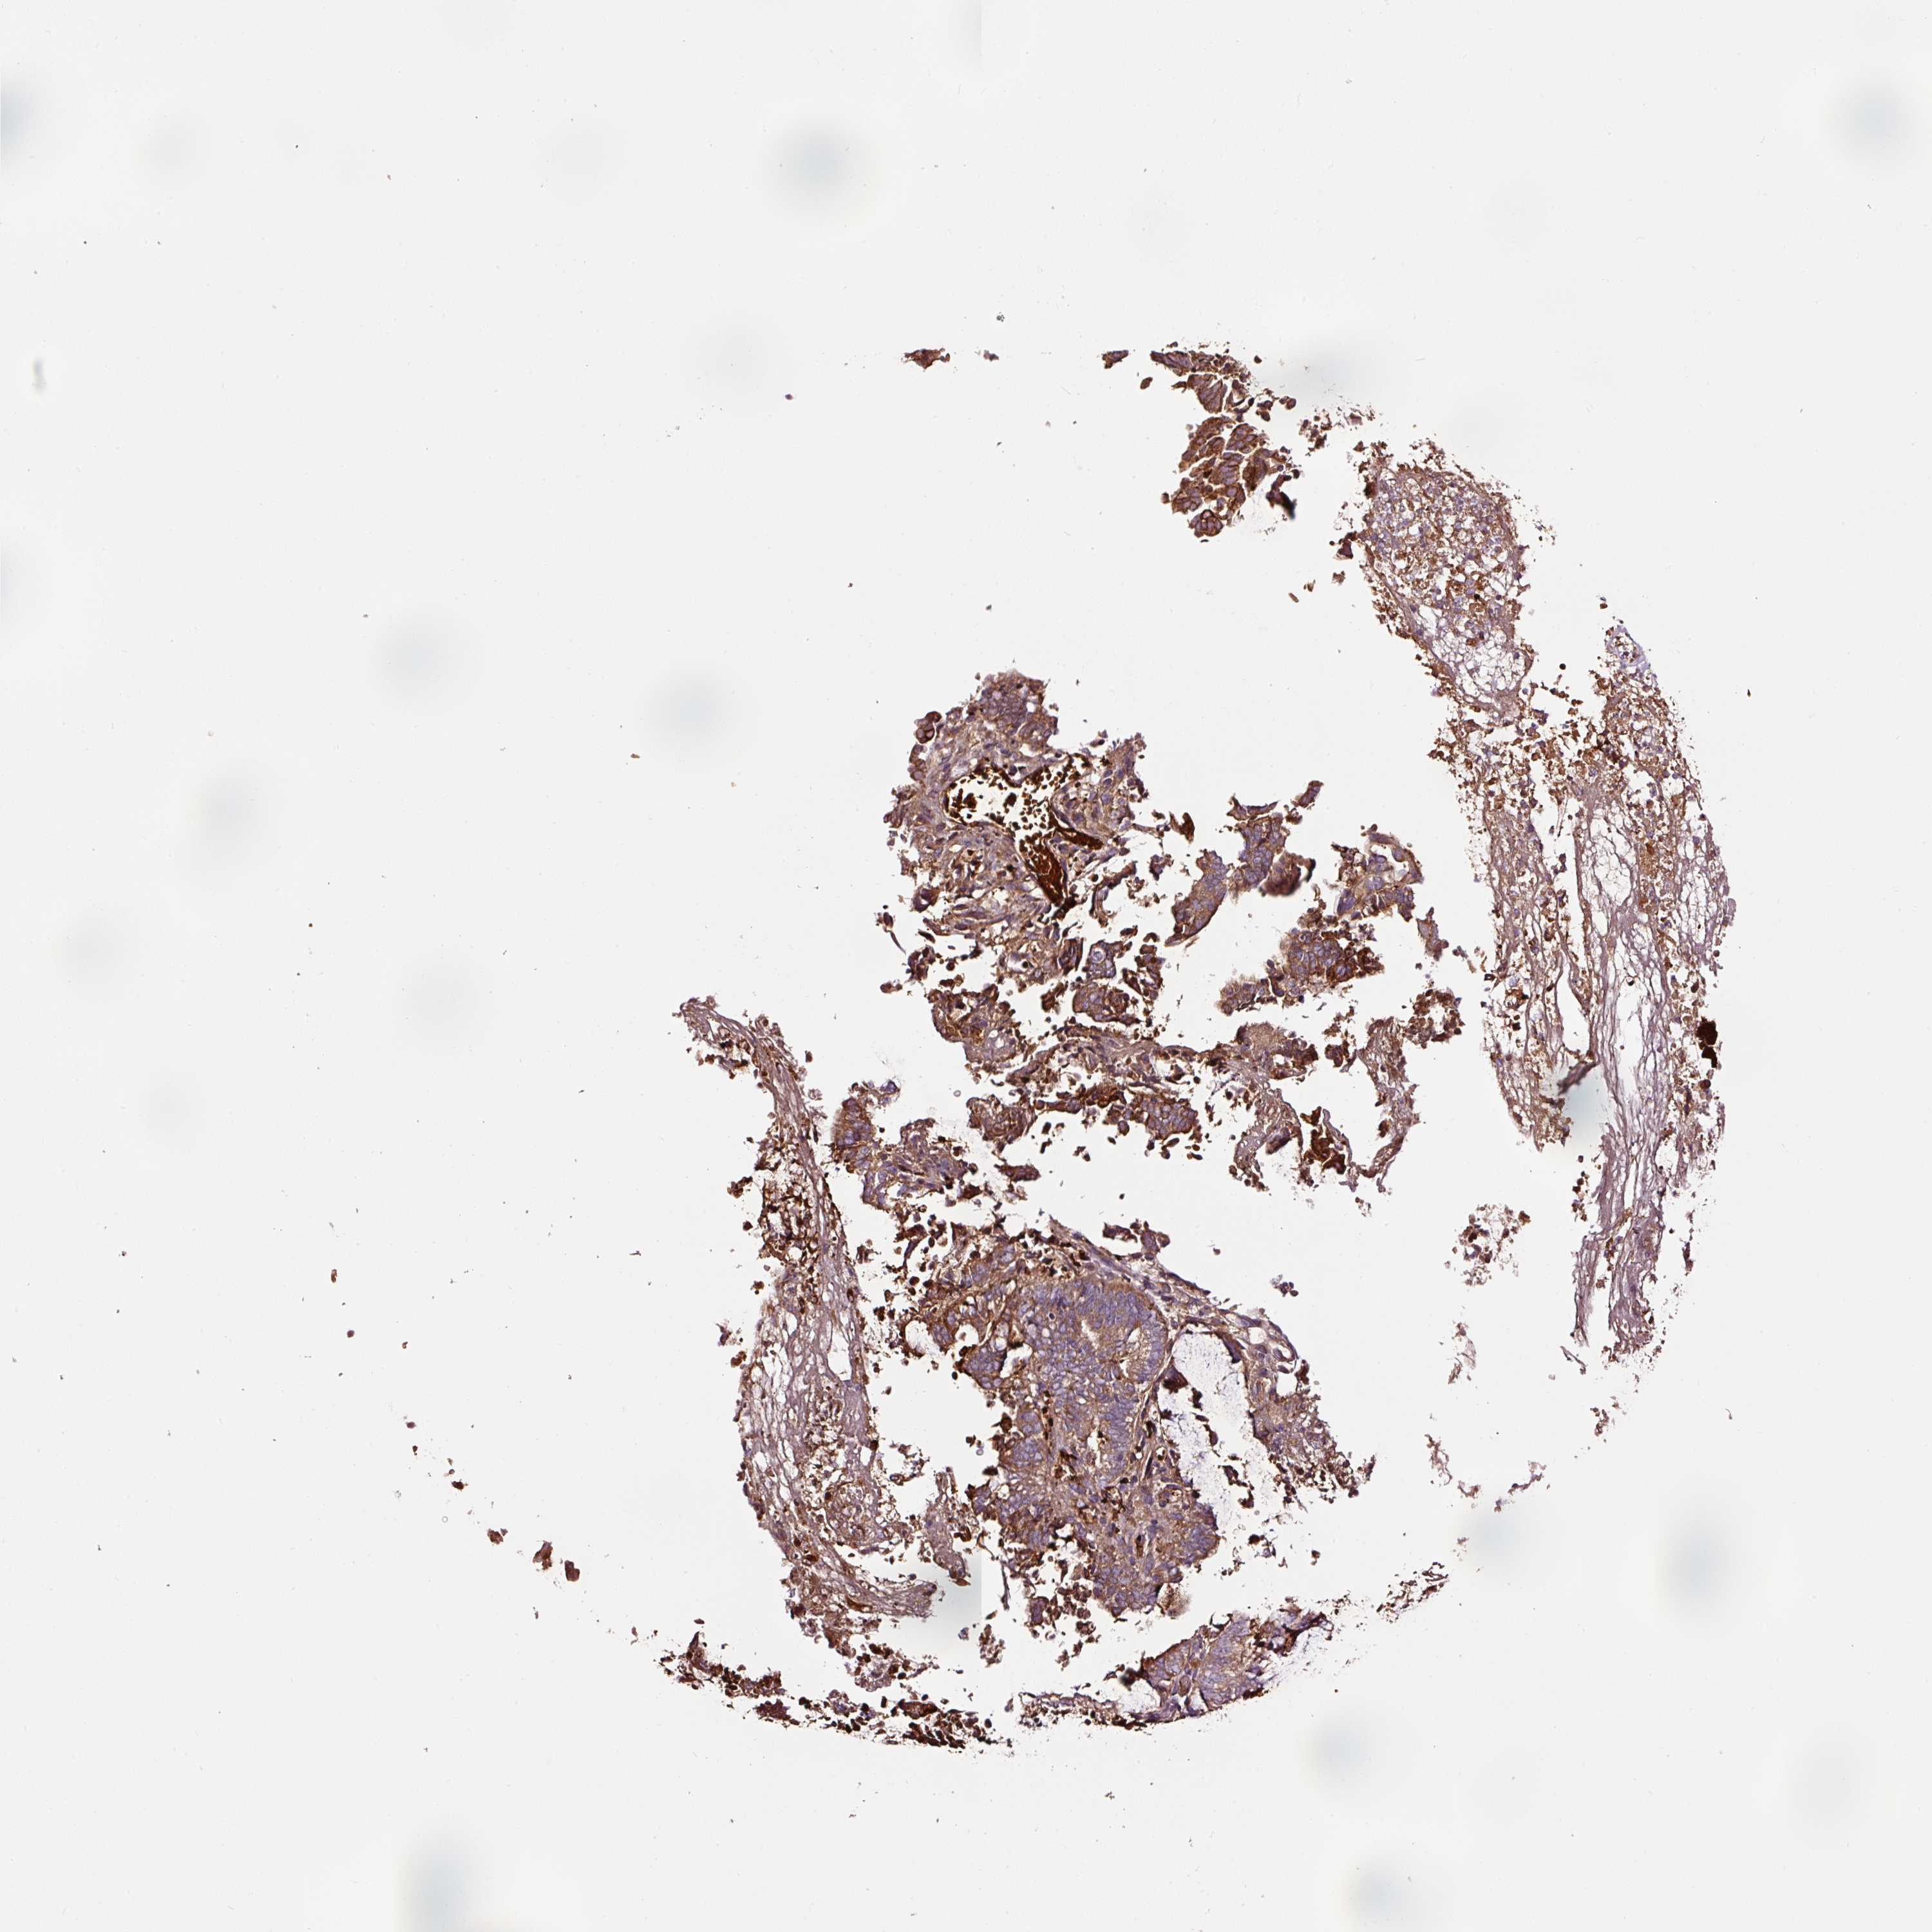

ENDOMETRIAL CANCER - Protein expressioni

A mouse-over function shows sample information and annotation data. Click on an image to view it in a full screen mode. Samples can be filtered based on level of antibody staining by selecting one or several of the following categories: high, medium, low and not detected. The assay and annotation is described here.

Note that samples used for immunohistochemistry by the Human Protein Atlas do not correspond to samples in the TCGA dataset.

Antibody stainingi

Antibody staining in the annotated cell types in the current human tissue is reported as not detected, low, medium, or high, based on conventional immunohistochemistry profiling in selected tissues. This score is based on the combination of the staining intensity and fraction of stained cells.

Each image is clickable and will lead to virtual microscopy that enables deeper exploration of all samples and also displays staining intensity scores, fraction scores and subcellular localization as well as patient and tissue information for each sample.

Antibody HPA046311

Antibody CAB033468

Staining

High

Medium

Low

Not detected

Intensity

Strong

Moderate

Weak

Negative

Quantity

>75%

75%-25%

<25%

None

Location

Nuclear

Cytoplasmic/membranous

Cytoplasmic/membranous,nuclear

Adenocarcinoma, NOS